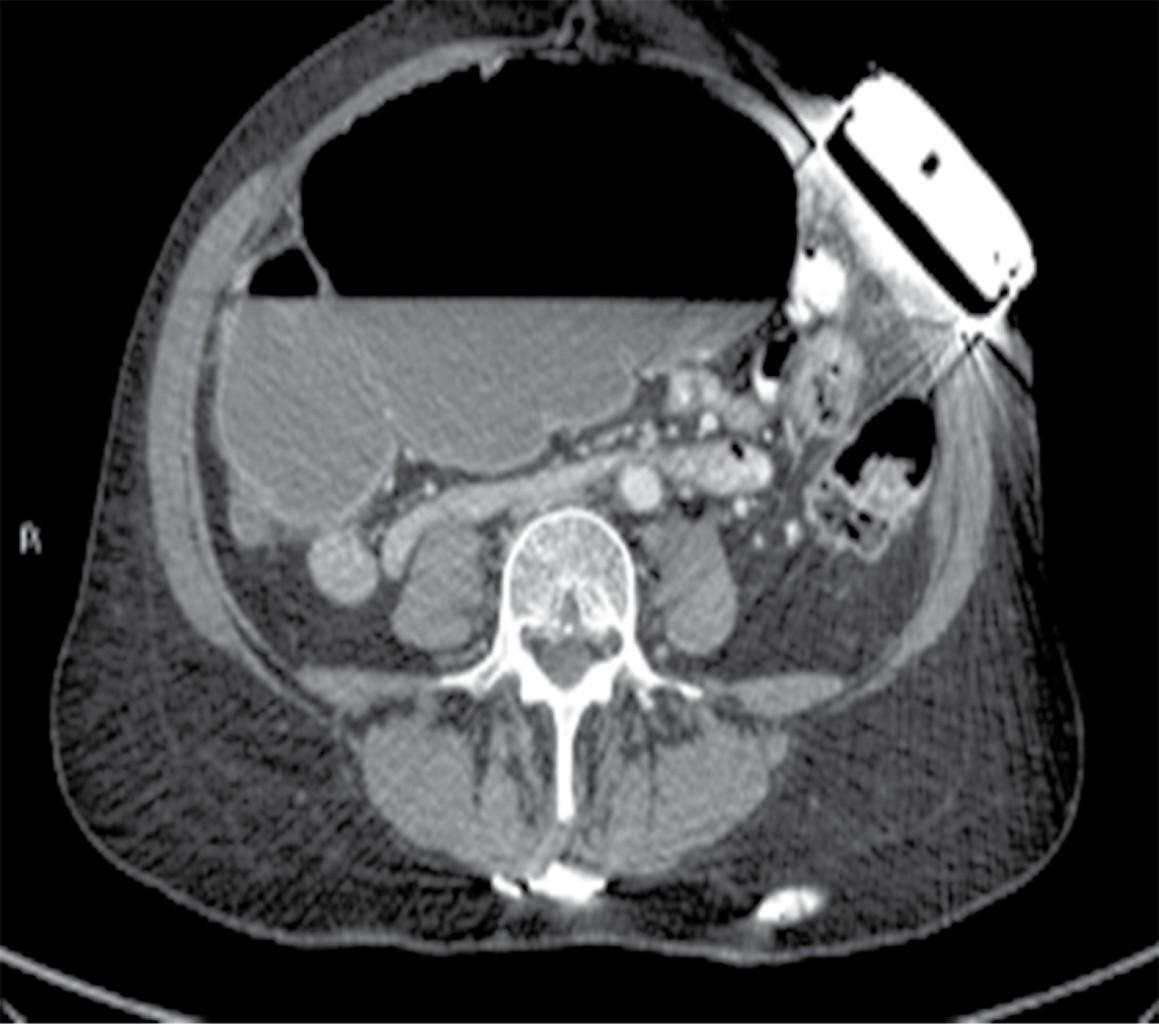

Se solicitaron estudios de laboratorio, los cuales reportaron 12,000 leucocitos por milímetro cúbico, siete bandas y niveles de lactato sérico de 2.8 mmol/l. Posteriormente se realizó una tomografía de abdomen con doble contraste, encontrando importante dilatación cecal, dilatación de colon ascendente y de la porción proximal de colon transverso, junto con una zona de transición hacia tercio distal, localizado en fosa iliaca izquierda. De igual manera, se encuentra hernia de pared abdominal supraumbilical en línea media con escaso tejido graso y epiplón (Figuras 1, 2, 3 y 4).

Figura 1